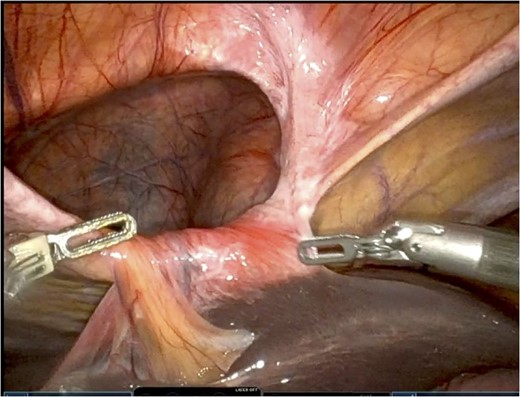

Care was taken to avoid injury to the pleura and the pericardium. Once the sac was reduced, the defect’s size was measured as 9 cm in horizontal length by 4 cm in vertical dimension. Primary closure of the defect was performed with a running 0 V-loc absorbable 180 suture.

Polypropylene ProGrip mesh was then cut to size to cover the primary defect. It was cut to 14 cm in horizontal dimension by 7 cm in vertical dimension, with rounded edges (Fig. 5).